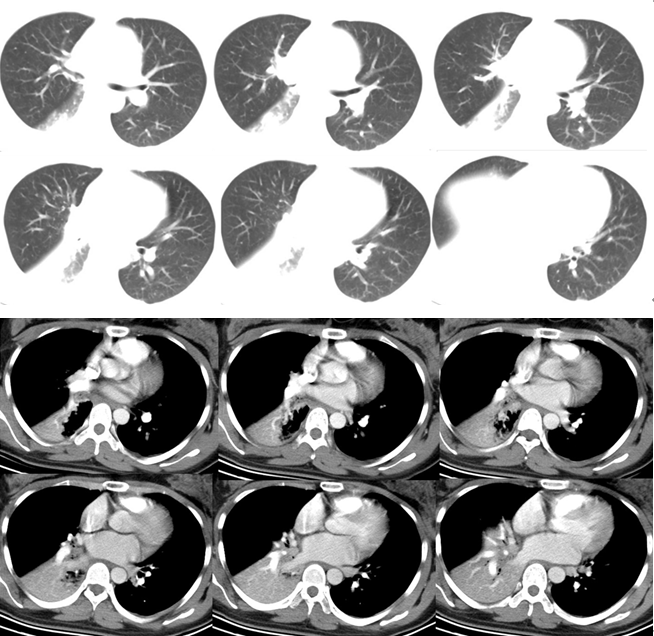

• 胸部增强CT(图1):(肺窗)右中叶和右下叶肺不张,(纵隔窗)除肺不张外,右中间段支气管、右中叶和下叶支气管管腔中可见多发的小片状高密度影,CT值约为50 Hu。考虑血栓堵塞可能性较大。右侧支气管动脉增粗,且有少许迂曲,其起源于胸主动脉前壁,通过隆突下,到右肺下叶近肺门处消失。

图片

图1  患者胸部CT

该患者大咯血诊断明确,而且出现了呼吸衰竭,住院期间给予酚妥拉明、氨甲环酸等保守治疗,效果不明显,症状进展。虽然垂体后叶素效果更佳,但由于其可引起子宫收缩,所以妊娠期女性禁用。增强CT已经提示可能存在支气管动脉畸形,结合其走行和出血部位,考虑这例患者是支气管动脉畸形导致的咯血可能性大,具有血管造影和后期介入栓塞治疗的指征。